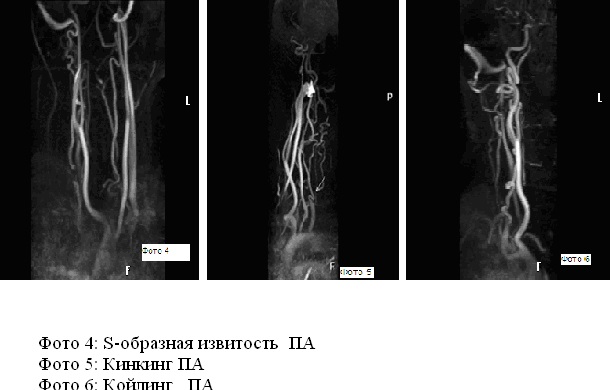

С изгиб вса

С изгиб вса 113 фото